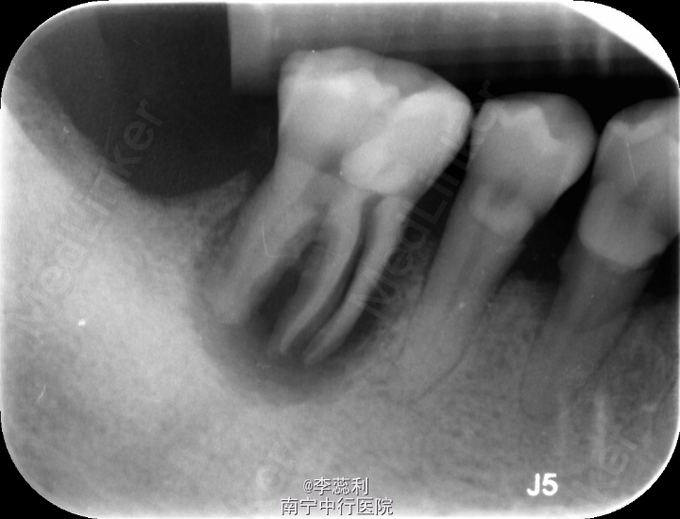

右下六咬合面牙色充填物,近中及颊侧深牙周袋,叩(+),松二度,X-Ray示:47近中根纵折,未见明显高密度充填物

46牙根纵折,建议拔除患牙

此例患者既往史不详,但是牙髓病变已经延伸至根尖,出现比较明显的根尖炎症和牙周病变